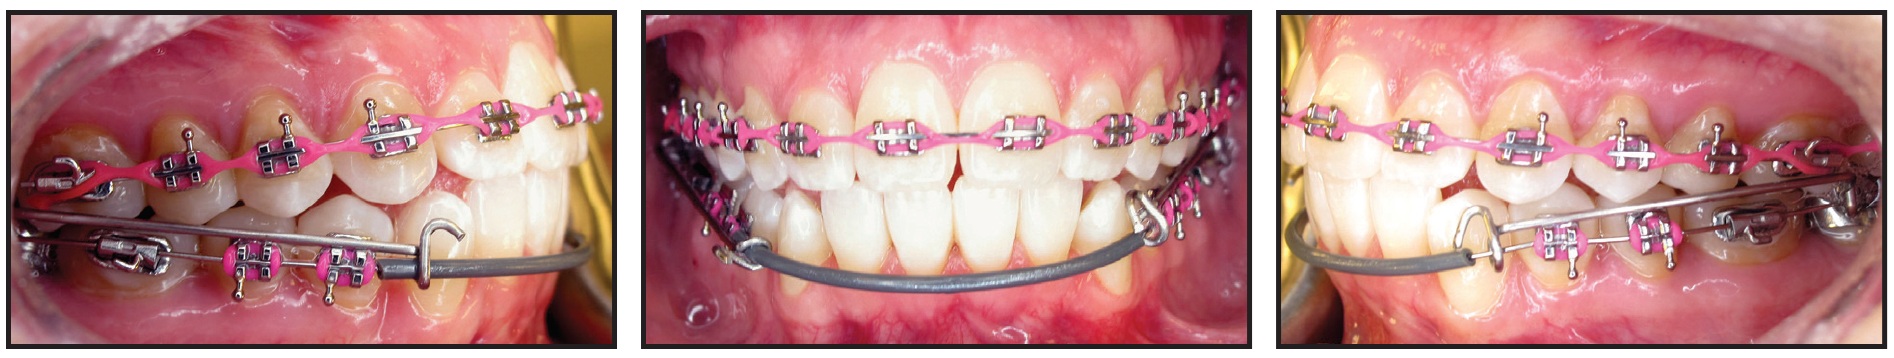

After another nine weeks of treatment, the remaining teeth were bonded (Fig. 9). Vertical elastics were worn from the upper canines to the lower canines and first premolars. Finishing and detailing were carried out prior to debonding, and IPR was performed from lower canine to canine to resolve the Bolton discrepancy.

Fig. 9 Remaining teeth bonded nine weeks later.

Total treatment time was 21 months (Fig. 10A). A normal overbite and overjet were established, while the Class I occlusion was maintained. The midlines were coincident, and a straighter profile was achieved. The patient showed slightly increased incisal angulations, proper root angulations, and normalized condylar positions with no further condylar remodeling. Cephalometric superimpositions indicated flaring of the upper and lower incisors and some mandibular protrusion (Fig. 10B).

Fig. 10 A. Patient after 21 months of treatment (continued in next image).

Fig. 10 (cont.) B. Superimposition of pre- and post-treatment cephalometric tracings.

A lower 3-3 retainer was bonded. Upper and lower Essix*** retainers were prescribed to be worn 24 hours per day (except while eating) for three months, after which the patient could switch to nightly wear. She reported no post-treatment TMD symptoms.